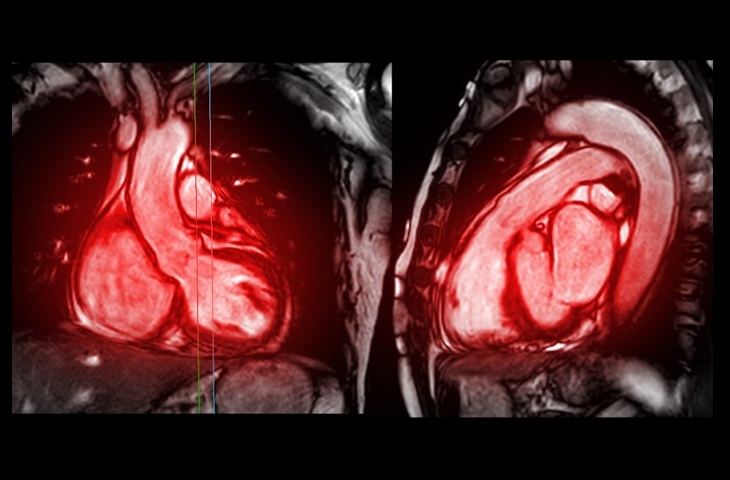

Además, las biopsias "ciegas" basadas en PSA pueden llevar al sobrediagnóstico de cánceres de crecimiento lento y clínicamente insignificantes, al mismo tiempo que pueden pasar por alto formas más agresivas de cáncer. Un enfoque alternativo es utilizar imágenes por resonancia magnética (RM) para identificar signos de tumores antes de decidir si es necesaria una biopsia, reservando las biopsias solo para los casos en los que se detectan anomalías. Un nuevo estudio para evaluar si el enfoque de RM primero es seguro a largo plazo ha descubierto que esta estrategia no representa ningún riesgo adicional para los pacientes durante al menos tres años.

El malestar asociado a las biopsias sistemáticas llevó a los investigadores de Charité – Universitätsmedizin Berlin (Berlín, Alemania) a investigar si la RM podía informar de manera confiable y segura las decisiones de biopsia en hombres con sospecha de cáncer de próstata, y si los hombres sin hallazgos anormales en la RM podían evitar de manera segura biopsias inmediatas y, en su lugar, continuar con un seguimiento clínico. En el estudio se incluyeron y controlaron casi 600 pacientes con sospecha de cáncer de próstata. Estos pacientes se sometieron a una exploración de RM multiparamétrica en Charité. Esta técnica avanzada de RM evalúa varios parámetros específicos del tejido, incluida la intensidad de las señales del tejido prostático, el flujo sanguíneo o la perfusión y la difusión de moléculas de agua en el tejido.

Un equipo de radiólogos expertos analizó las imágenes de RM y solo se tomaron muestras de tejido si la RM mostraba hallazgos sospechosos en la próstata. Los pacientes con resultados normales de la RM se sometieron a controles urológicos regulares durante un período de tres años. Esto permitió a los investigadores evaluar si la "vía de la resonancia magnética" era una alternativa segura a las biopsias. El estudio, publicado en JAMA Oncology, concluyó que este enfoque, en el que los resultados normales de la RM se acompañan de controles urológicos de rutina, era altamente confiable. El estudio mostró que el 96 % de los pacientes con resultados normales de la RM no desarrollaron cáncer de próstata agresivo en tres años. Solo el 4 % de aquellos con resultados iniciales negativos en la RM fueron diagnosticados con cáncer de próstata agresivo durante el monitoreo posterior.